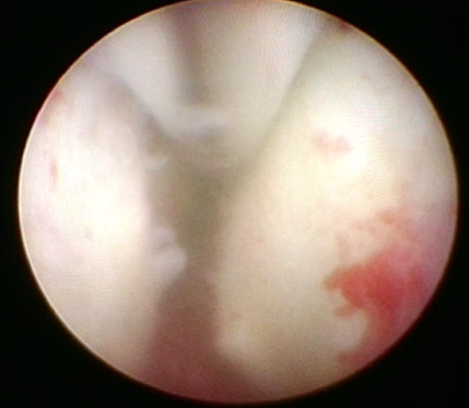

수술 전 후 전립선 요도

수술 전 비대조직으로 막힌 전립선요도

수술 후 3개월 뒤 잘 열린 전립선요도